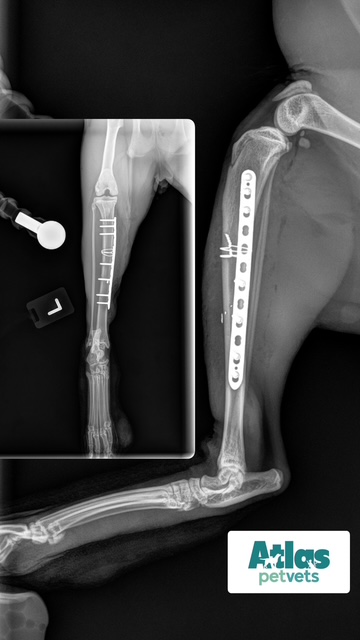

Fracture Repair

We provide surgical fracture repair for many types of broken bones. Treatment plans are individualized based on the location and complexity of the fracture, your pet’s age and size, and overall health.

Radius Fracture Before #1

Radius Fracture Before #2

Radius Fracture After

Large Dog Radius Fracture Before

Large Dog Radius Fracture After #1

Large Dog Radius Fracture After #2